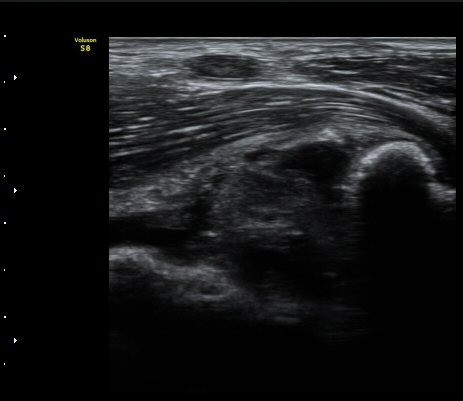

[ÆÈ²ÞÄ¡] ÆÈ²ÞÄ¡ °üÀý³» À¯¸®Ã¼¿¡ ÀÇÇÑ ÆÈ²ÞÄ¡ ÅðÇ༺ °üÀý¿°

¼ºº° / ³ªÀÌ

³²ÀÚ/ 44¼¼

ÁÖÁõ»ó

ÆÈ±ÀÄ¡ ÅëÁõ

ÃÊÀ½ÆÄ °Ë»ç